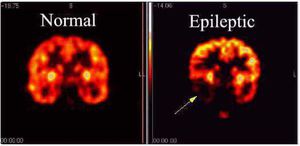

Epileptic

Epilepsy is a common and diverse set of chronic neurological disorders characterized by seizures Some definitions of epilepsy require that seizures be